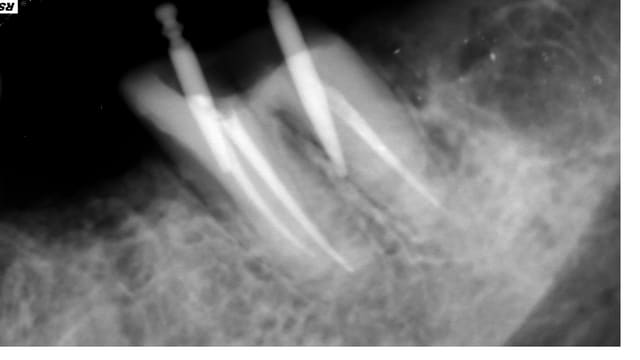

Preparation logement de tenon sur 37 sur traitement endodontique ancien non réalisé par mes soins .

A la retro alveolaire avant prise d'empreinte , mon axe est completement foireux .

Absence de saignement et de douleur , je pense donc qu'il n'y a pas de perforation , je decide d'obturer a la gutta - condensation à chaud

ta radio post retraitement montre bien qu'il y a eu perforation...

Je suis d'accord radiologiquement pour la perforation mais clinique réellement aucun saignement - peut etre en foulant la mince paroi de dentine a du lacher ...

Sur ta réobturation on voit qu'il y a bien une perfo.